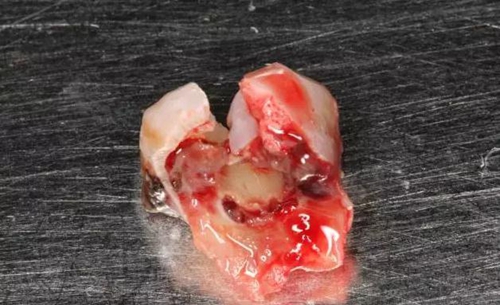

圖8.拔除的37頰側(cè)的牙根完全被壓迫吸收完。

8.jpg